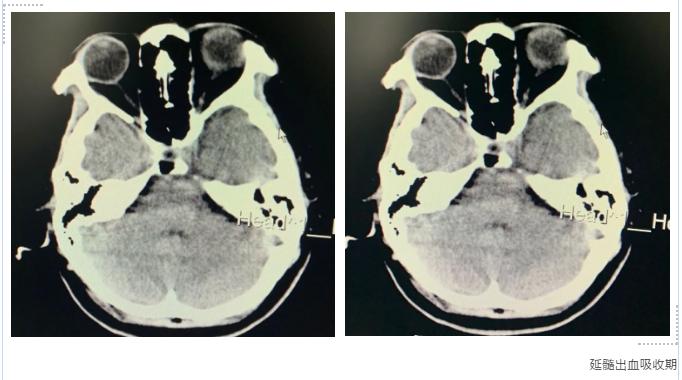

(2) 血腫位置:延髓出血預(yù)后最差。

尹阿姨還算幸運(yùn),出血的部位在腦干的橋腦區(qū)。癥狀雖然很重,但并沒有影響到呼吸、循環(huán)等重要系統(tǒng)。

在轉(zhuǎn)到我院積極治療兩周后,復(fù)查頭顱CT,血腫逐漸吸收。復(fù)視、肢體無力、麻木和后枕部疼痛感明顯改善。

有次去查房,尹阿姨說“我這后腦勺被棍子打的感覺終于消失了”。